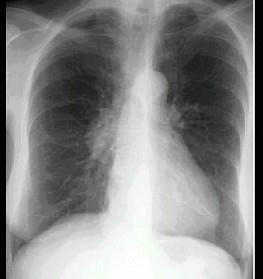

问题 男,67岁,无明显症状,胸片检查发现病变,进一步行CT检查如图,其最可能的诊断为 ( )

选项 A、后纵隔神经源性肿瘤 B、右侧胸膜间壁瘤 C、右下肺周围型肺癌 D、右下肺错构瘤 E、右下肺炎性假瘤

答案 A